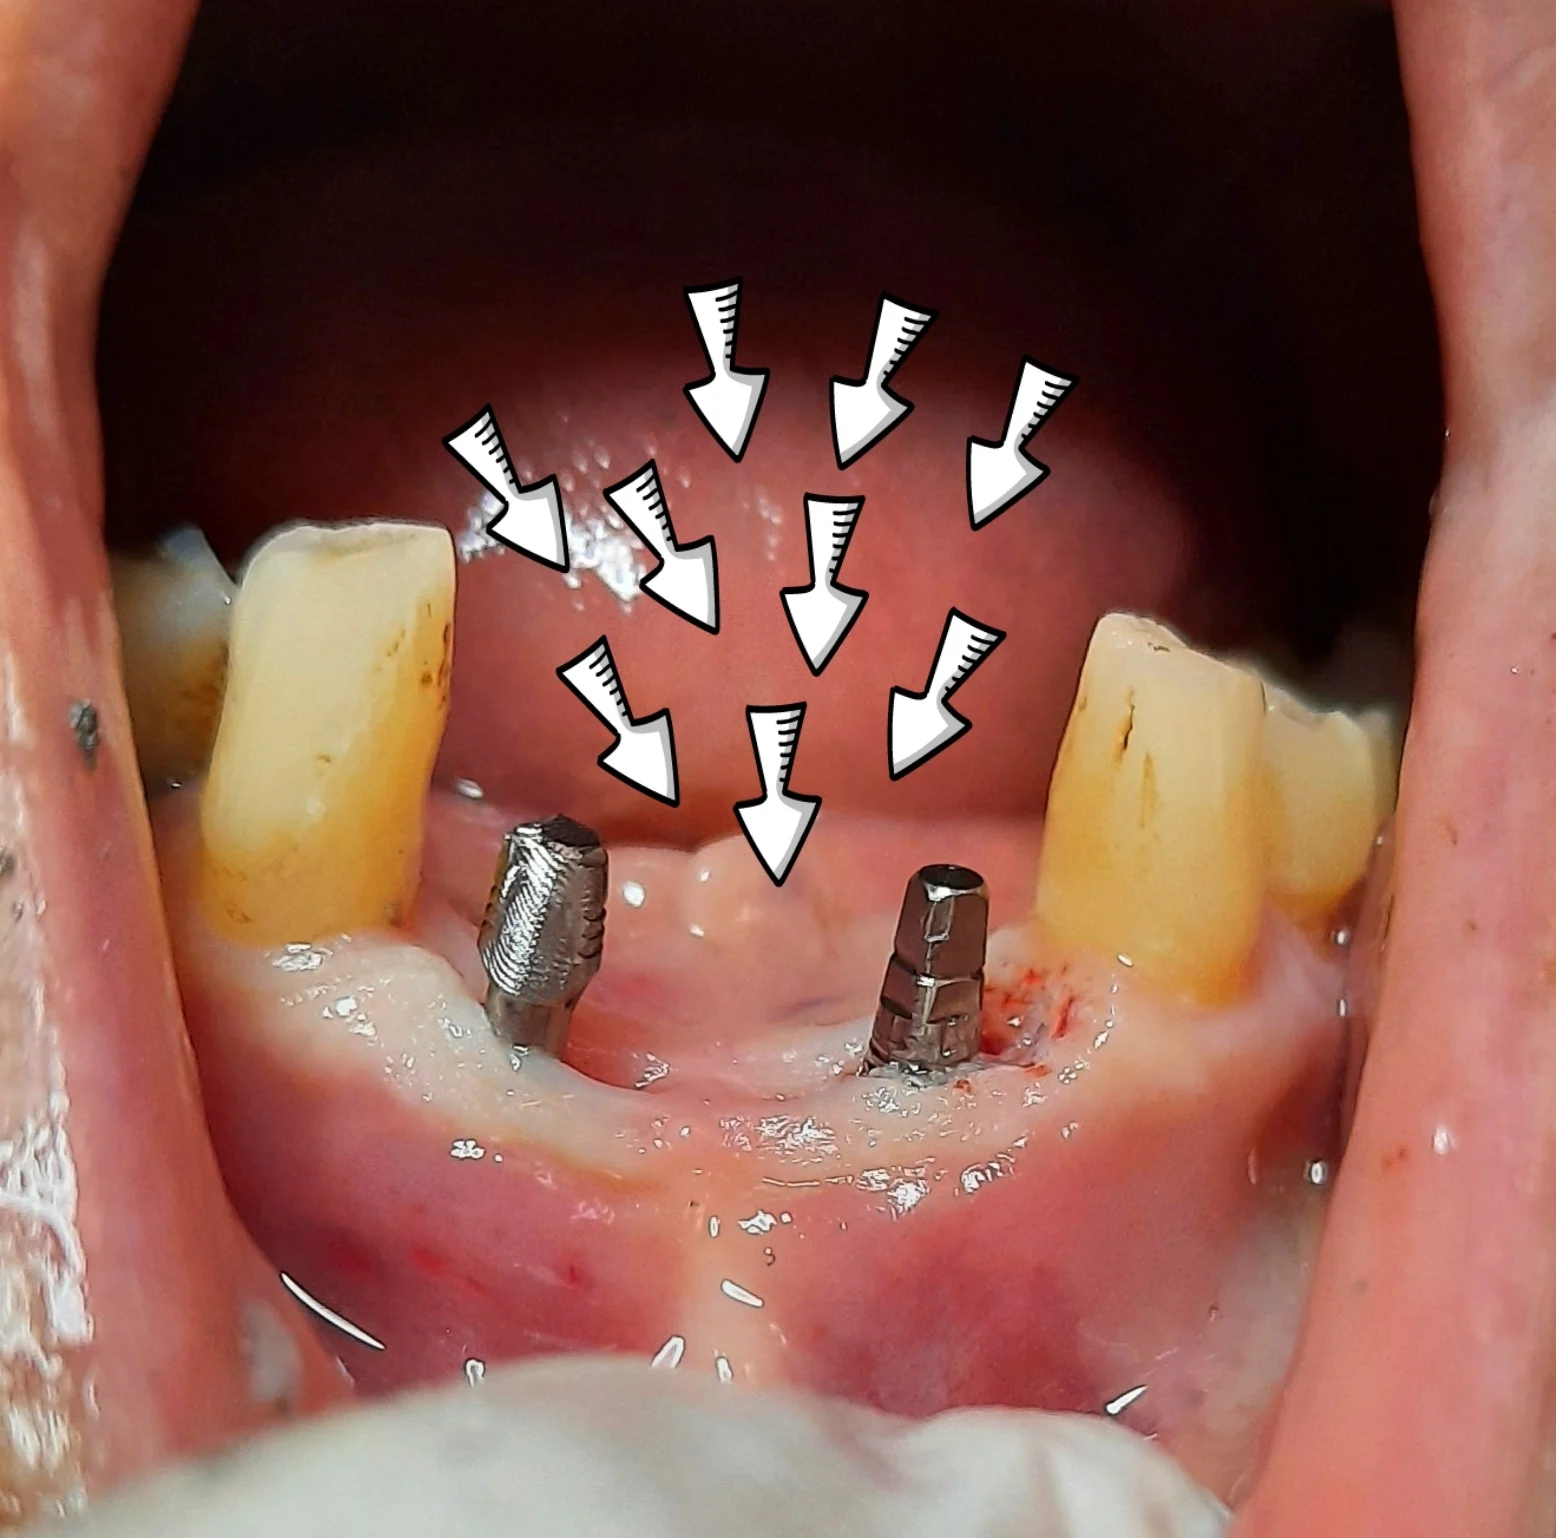

*המרפאה מבצעת השתלות שיניים, קומפרסיבים והעמסה מיידית בשיטה חדשנית, כולל שיקום תוך שבוע ימים.

*השתלות שיניים ביום אחד, גם למי שסובל ממחסור בעצם, כאשר ישנה אחריות מלאה על השתלים ועל הטיפולים.